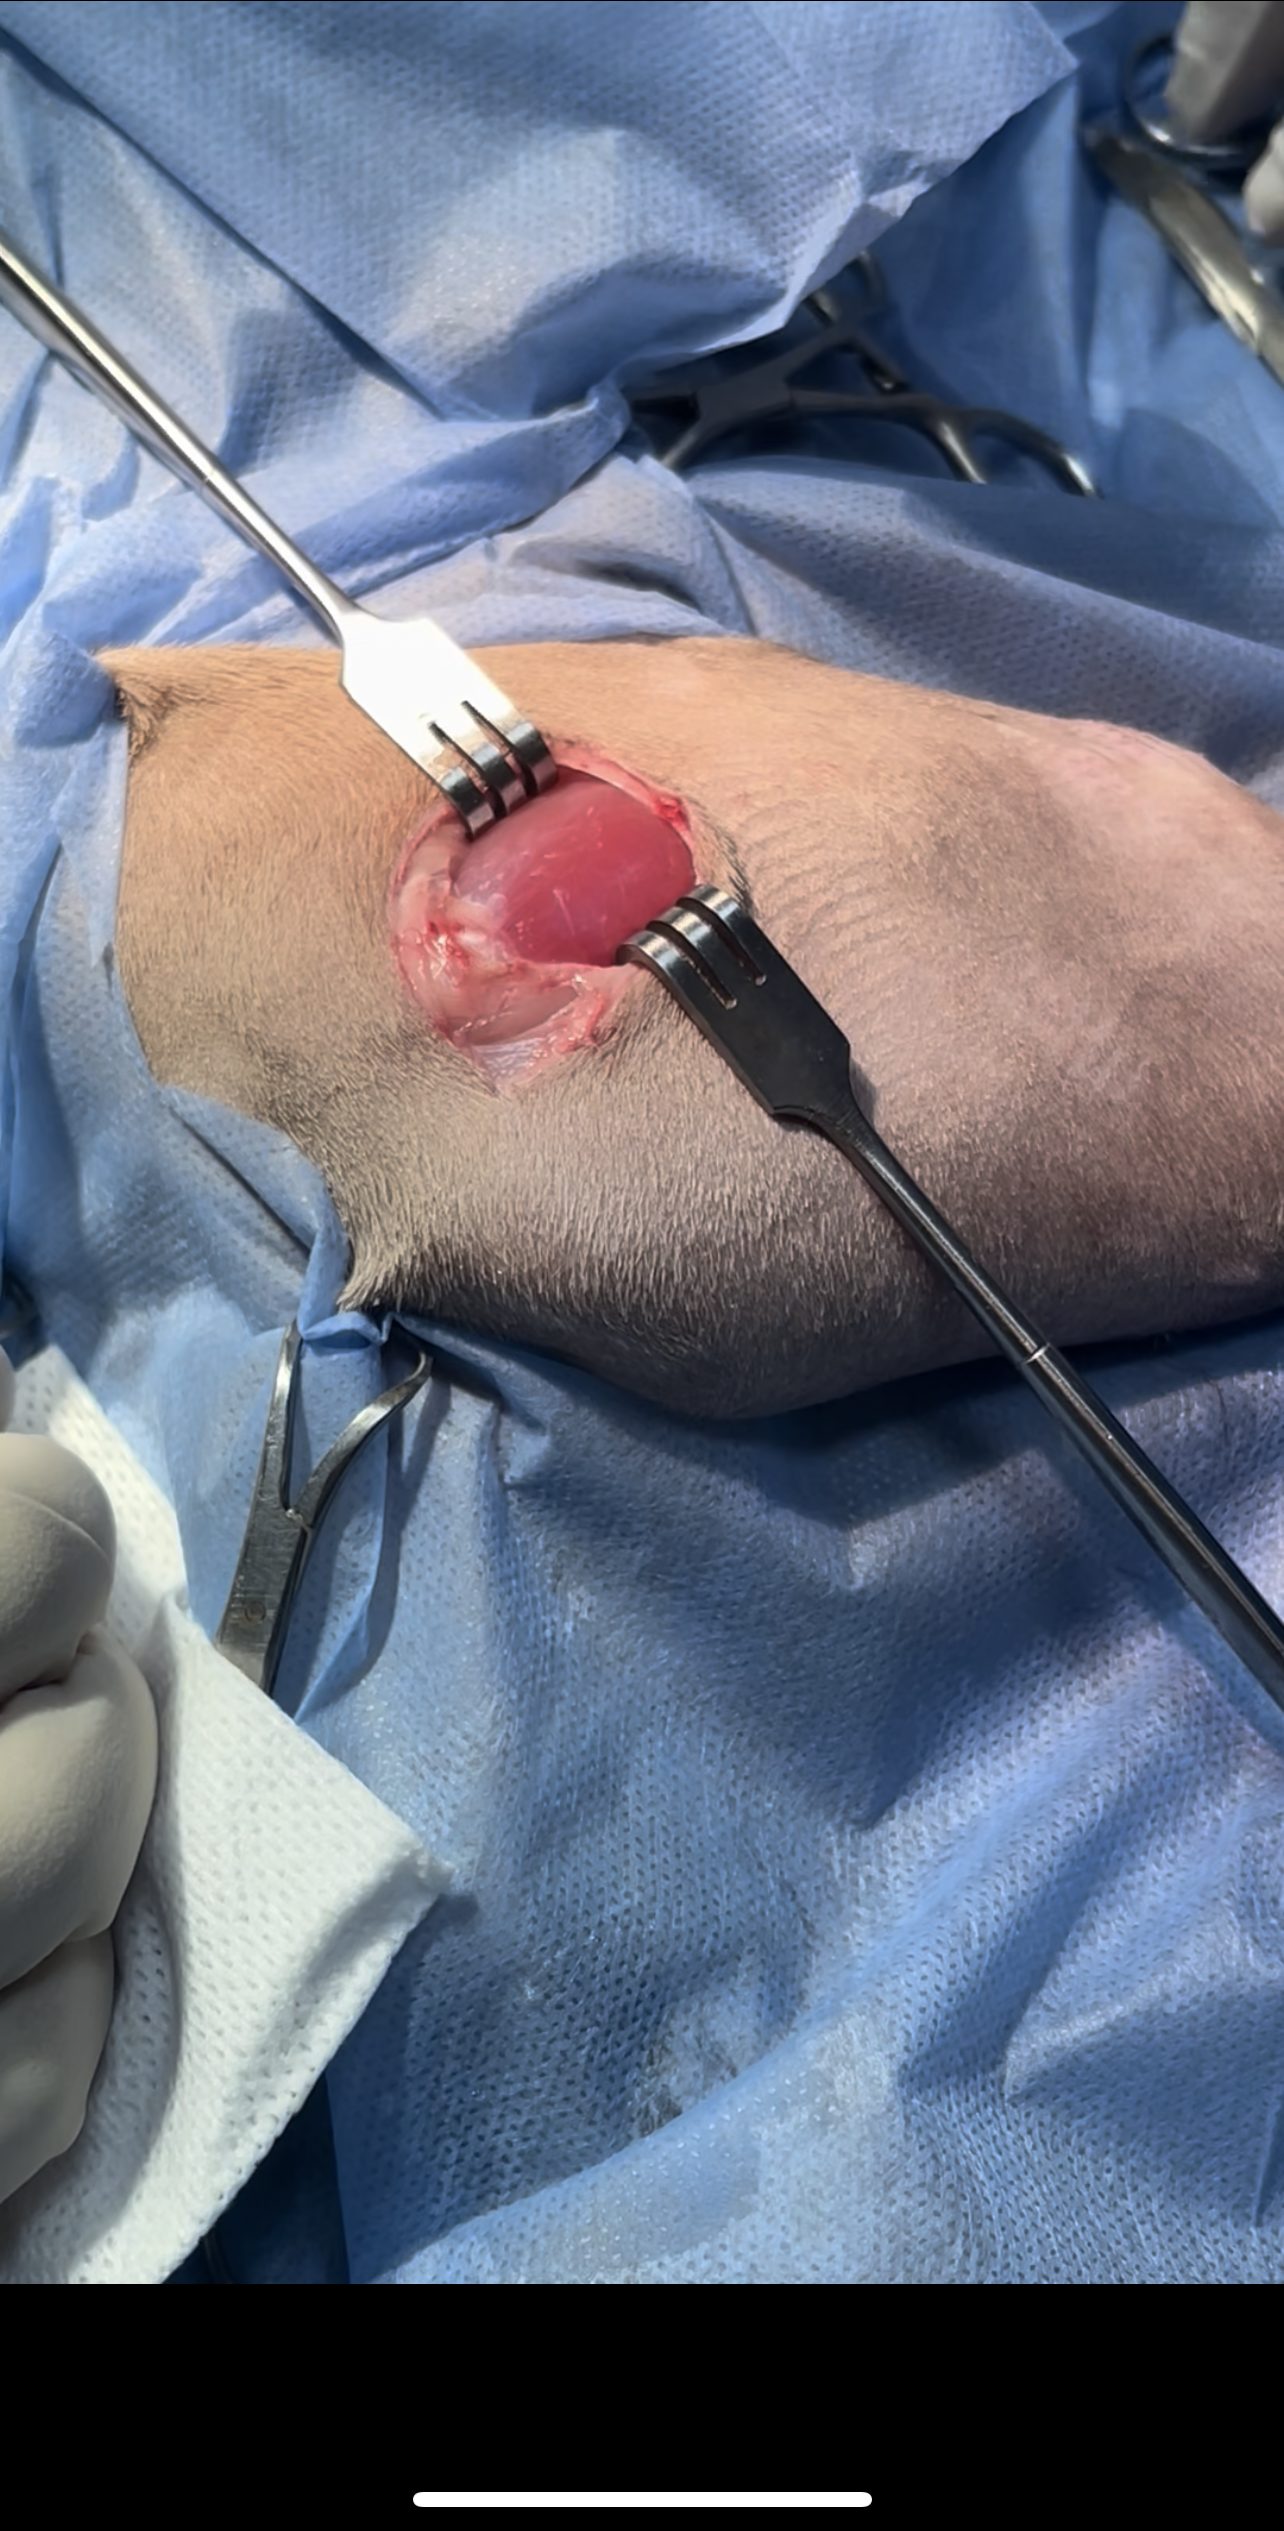

Femoral Head and Neck Ostectomy (FHO) is a salvage surgical procedure performed to eliminate pain and restore functional limb use in animals suffering from severe hip joint

disease

The surgery involves removing the femoral head and neck, thereby eliminating bone-to-bone contact and allowing a fibrous pseudoarthrosis (“false joint”) to form

Bilateral FHO was recommended starting with the right most affected limb and the other to be scheduled after 2 months